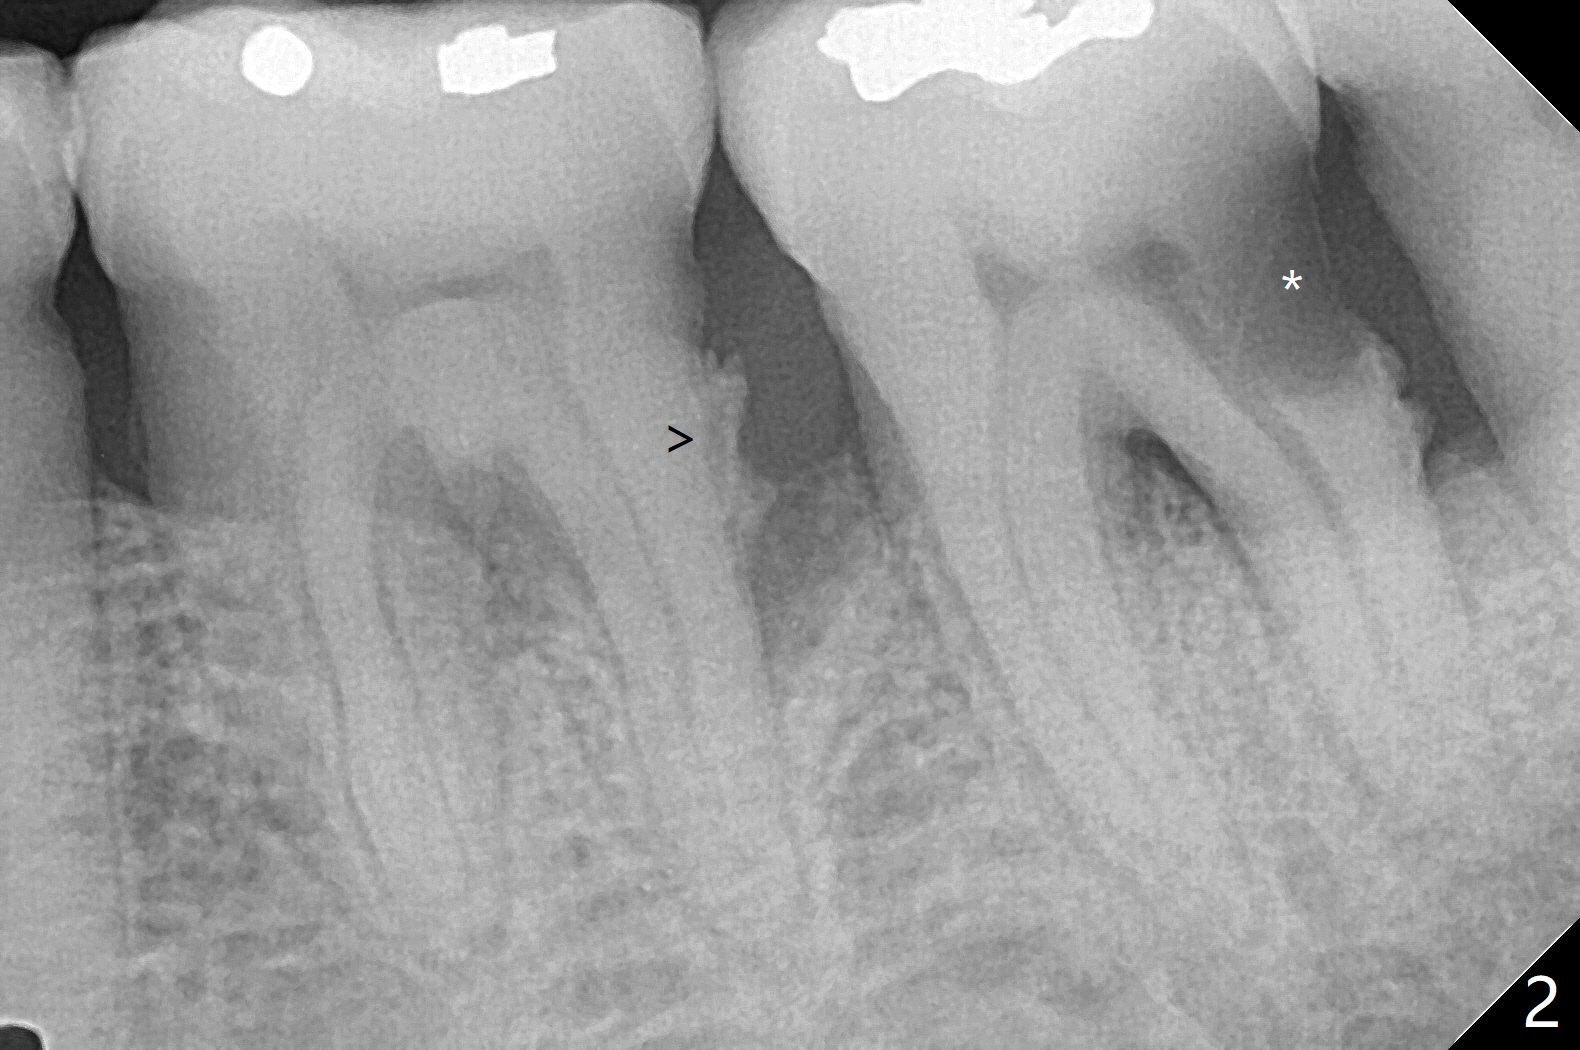

60岁男,吸烟,口腔卫生不好,不积极配合治疗,下前牙两个植体螺纹暴露,但是没有症状。两年中,左下七(图一,二)不能保留(图三),虽然六远中结石被清除(图三>),七位点保留(图四 *)时未能顺便在六远中填入骨粉(用血混合,胎盘膜覆盖)。四五个月后,七种植时将钻头骨粉放置于六远中缺损处,如何才能让骨粉在患处生根发芽?术后一个月,去除树脂敷料后,最表面骨粉未能被整合,下面骨粉好像已经与肉芽组织结合了(图五),其实根尖片应该拍摄证实这一点。吸烟者血供不好,愈合欠佳。术后三个月牙槽嵴宽(图六);高度稍微减低(图七)。术后4个月CT显示近中牙槽窝正好位于缺牙区正中(图八),所以植体必然进入近中窝(图九)。